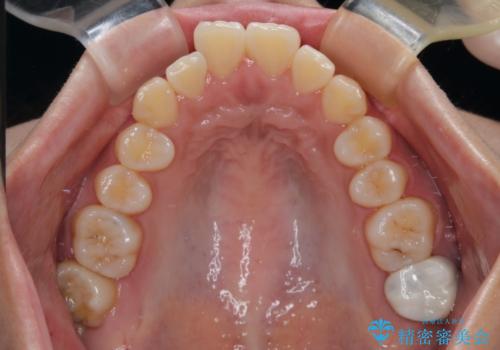

- 前歯のデコボコと口元の突出感を気にして来院された患者様です。

上下前歯がくちばしのように突出していたため、上下左右の第一小臼歯4本を抜歯し、ワイヤー装置にて矯正治療を行うこととしました。

口元の突出感が改善されてことで、下唇に引っかかっていた上顎前歯も気にならなくなりました。